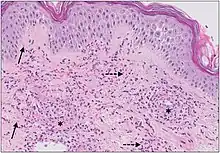

The small vessels in the skin affected are located in the superficial dermis and include arterioles (small arteries carrying blood to capillaries), capillaries, and venules (small veins receiving blood from capillaries).[5] In general, immune complexes deposit in vessel walls leading to activation of the complement system. C3a and C5a, proteins produced from the complement system, attract neutrophils to the vessels.[9] Once activated, neutrophils then release preformed substances, including enzymes causing damage to vessel tissue.[9] Evidence of this process can be seen with a sample of removed skin tissue, or biopsy, viewed under a microscope. Neutrophils are seen surrounding blood vessels and their debris within vessel walls, causing fibrinoid necrosis. This finding on histological examination is termed "leukocytoclastic vasculitis".[5]